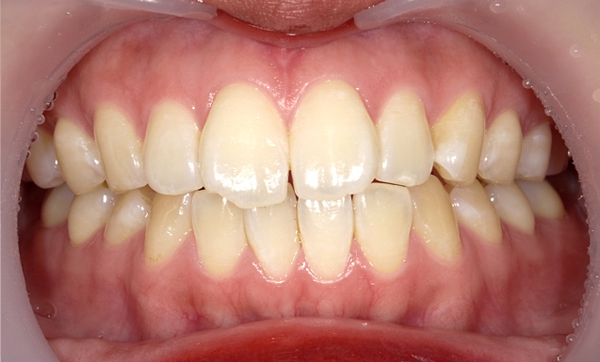

症例_009 「上下の前歯」症例

治療期間:7ヶ月金額:54万円+税20代女性捻転歯一部の反対咬合前歯のガタガタ

Before | After |

---|---|